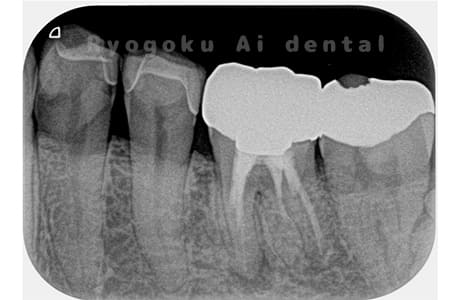

Case02

- 原因

- 慢性根尖性歯周炎

- 治療期間

- 3ヶ月

- 治療内容

- マイクロエンド

- 治療費用

- 121,000円

噛むと痛みが出る、とのことで来院した患者様です。他院での根管治療を終えてましたが、根尖病変を認めるため、マイクロエンドを行いました。

<リスク・副作用>

術後は痛み、腫れ、痺れなどの副作用が生じる場合があります。症状が再発する可能性があります。